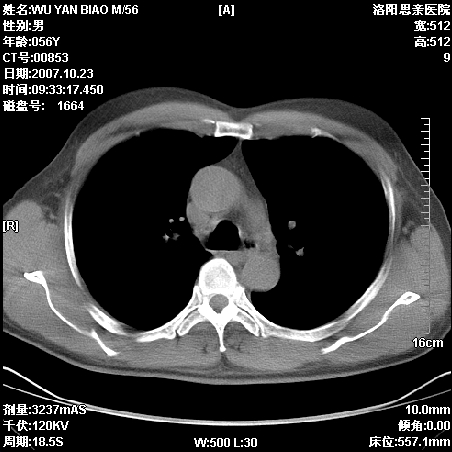

标题: CT10160:M56Y,体检发现,病人无不适,病人随访中 [打印本页]

标题: CT10160:M56Y,体检发现,病人无不适,病人随访中

后上纵隔占位,与肺交界清,宽基底附着脊柱,密度均匀,局部骨质无明确改变.

考虑;神经源性肿瘤,---起源交感n链?,不除外肠源性囊肿.

1、病灶在后纵隔脊柱旁沟内,此处是神经原性肿瘤的好发部位

2、病灶边缘光滑整齐,更说明病灶来于纵隔,由于有胸膜的包裹所以才导致这么光滑的边缘

3、病灶内的密度均匀